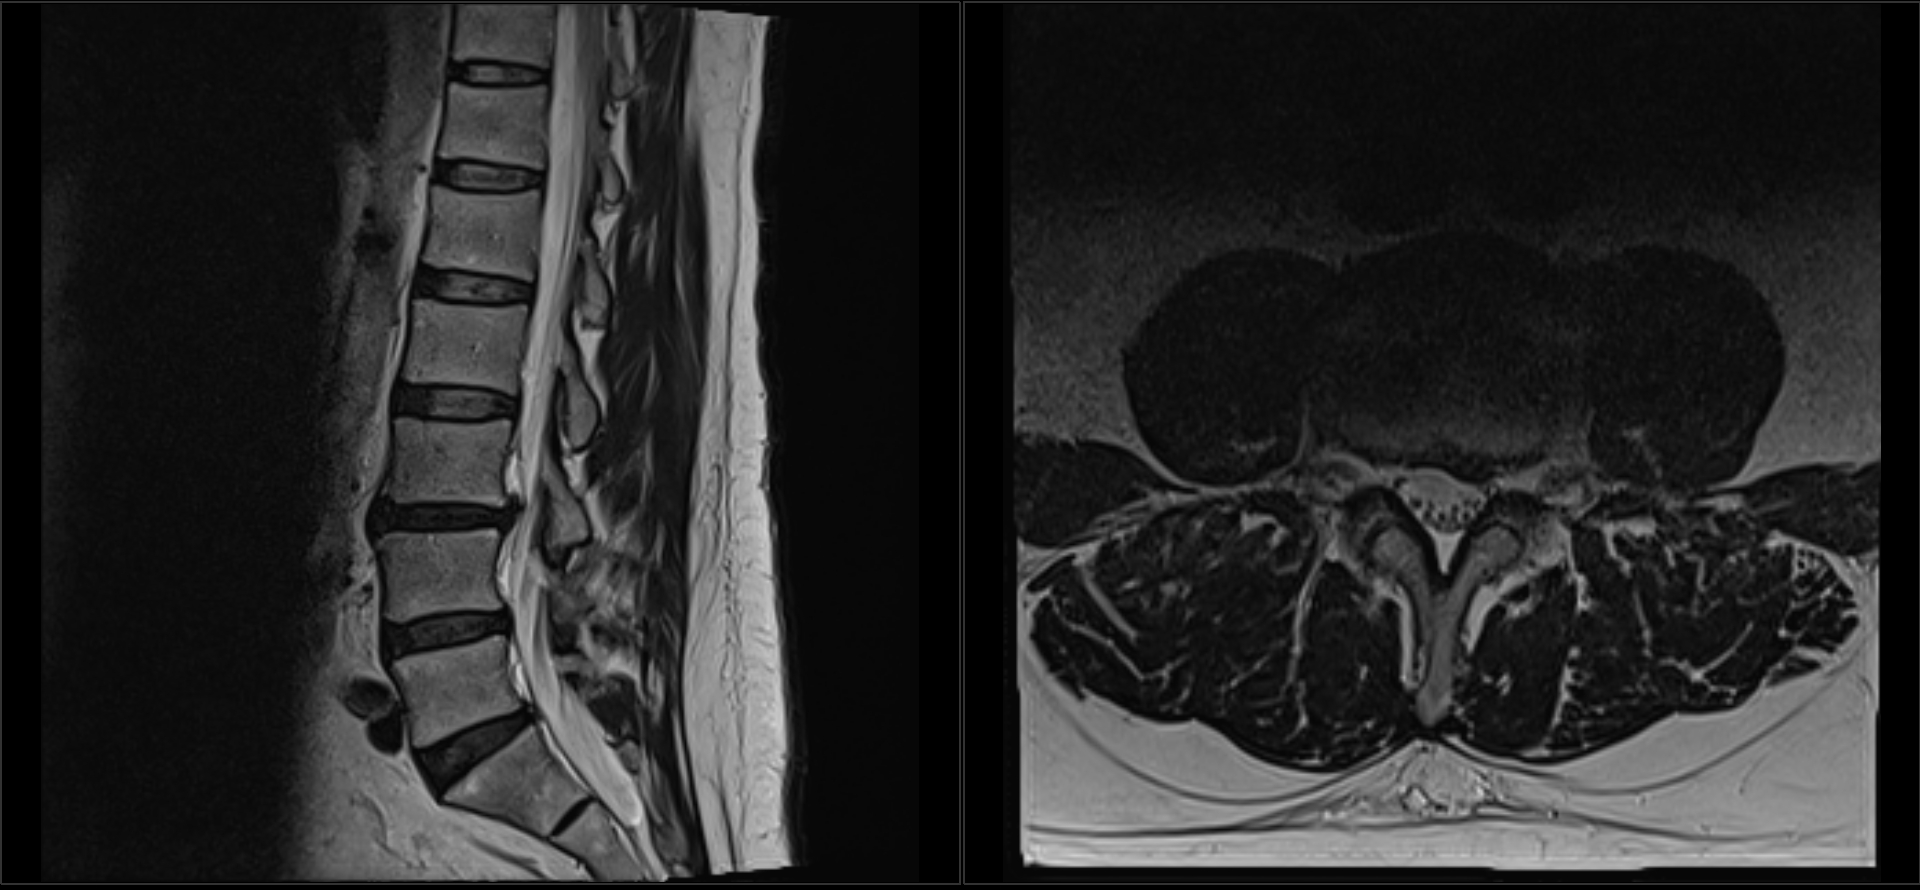

MRI Review, Done Right

If you already have an MRI, we don’t just read the radiology report. We review the actual images.

Then we:

• Correlate what we see on MRI

• Compare it with your motion X-rays

• Tie it back to your exam findings

This lets us identify the actual pain generator, not just what the report says might be abnormal.